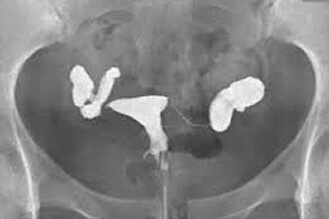

正常输卵管摄影,双侧输卵管通畅